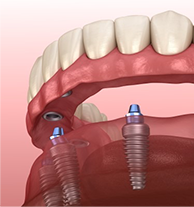

placed once healing allows, using Yomi® robotic guidance for precision in compromised bone.

implants, grafts, or maxillofacial prosthetics to restore chewing, speech, and facial contours.

With careful planning, hyperbaric oxygen protocols when needed, and robotic guidance, implant success is high.